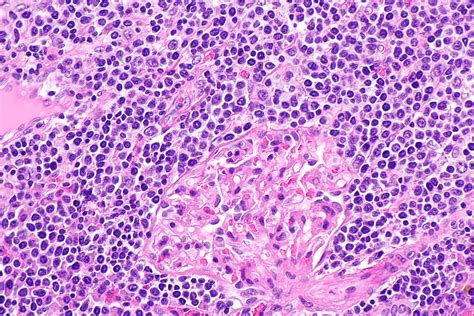

The Defining Difference: Reed-Sternberg Cells

The primary distinction between Hodgkin lymphoma and non-Hodgkin lymphoma lies in the specific type of lymphocyte involved and how they appear under a microscope. This is the cornerstone of the Hodgkin vs Non-Hodgkin classification.

• Hodgkin Lymphoma: This type is characterized by the presence of a specific, abnormal cell called the Reed-Sternberg cell. These are large, cancerous B cells that have become abnormally large and multinucleated. If a pathologist does not find these specific cells, the diagnosis is typically categorized as non-Hodgkin lymphoma.

• Non-Hodgkin Lymphoma: This is a more diverse group of cancers. It does not contain Reed-Sternberg cells. Instead, NHL involves a wide array of different types of abnormal lymphocytes (either B cells or T cells). Because there are so many subtypes of NHL, the behavior of the disease can vary dramatically from person to person.

Diagnosing lymphoma requires a meticulous approach, usually starting with a physical examination and imaging tests like CT or PET scans. However, the definitive diagnosis is always made through a biopsy. During a biopsy, a surgeon removes a lymph node or a portion of tissue to be examined in a laboratory. A pathologist then performs specialized tests, such as immunohistochemistry, to look for the presence of Reed-Sternberg cells, helping to clarify whether the patient has Hodgkin or non-Hodgkin lymphoma. Additionally, genetic testing of the cells can help identify the specific subtype of NHL, which is critical for determining the most effective targeted therapy.